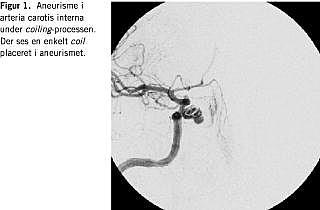

To dage senere blev patienten atter indbragt pga. akut epistaxis i hjemmet, blødningen var ophørt inden ankomsten til hospitalet, og patienten blev optransfunderet med fire portioner blod. Der blev foretaget rinoskopi med optik, og computertomografi (CT) af bihulerne. Bortset fra sløring i sinus sphenoidalis viste disse undersøgelser normale forhold. På denne indlæggelses ottende dag blev patienten fundet bevidstløs på gulvet efter fornyet epistaxis, anslået blødning ca. to liter. Hun blev optransfunderet med syv portioner blod, og der blev foretaget sinoskopi i universel anæstesi. Ved denne blev der set en blodstribe fra ostiet ud for sinus sphenoidalis, hvorfor dennes forvæg blev reseceret. I bunden af sinus sphenoidalis fandt man uregelmæssigt pulserende væv, og opera-tionen afsluttedes. Efterfølgende blev der foretaget magnetisk resonans (MR)-angiografi som viste et 1 cm stort aneurisme, der udgik fra a. carotis interna på højre side. Patienten blev overflyttet til Røntgendiagnostisk Afdeling på Odense Universitetshospital, hvor en arteriografi viste et topuklet aneurisme, der udgik fra højre a. carotis internas medial og forvæg og derfra eroderede ned i sinus sphenoidalis. Der blev i samme seance foretaget coiling af aneurismet via a. femoralis (Figur 1 ). Der opstod kortvarig central facialisparese, venstresidig svælgparese og venstresidig positiv babinskirefleks. Ved kontrol et halvt år efter coiling blev der fundet normale neurologiske forhold, og der var ikke siden blødningsepisoder. En kontrolarteriografi viste, at aneurismet var vellukket.